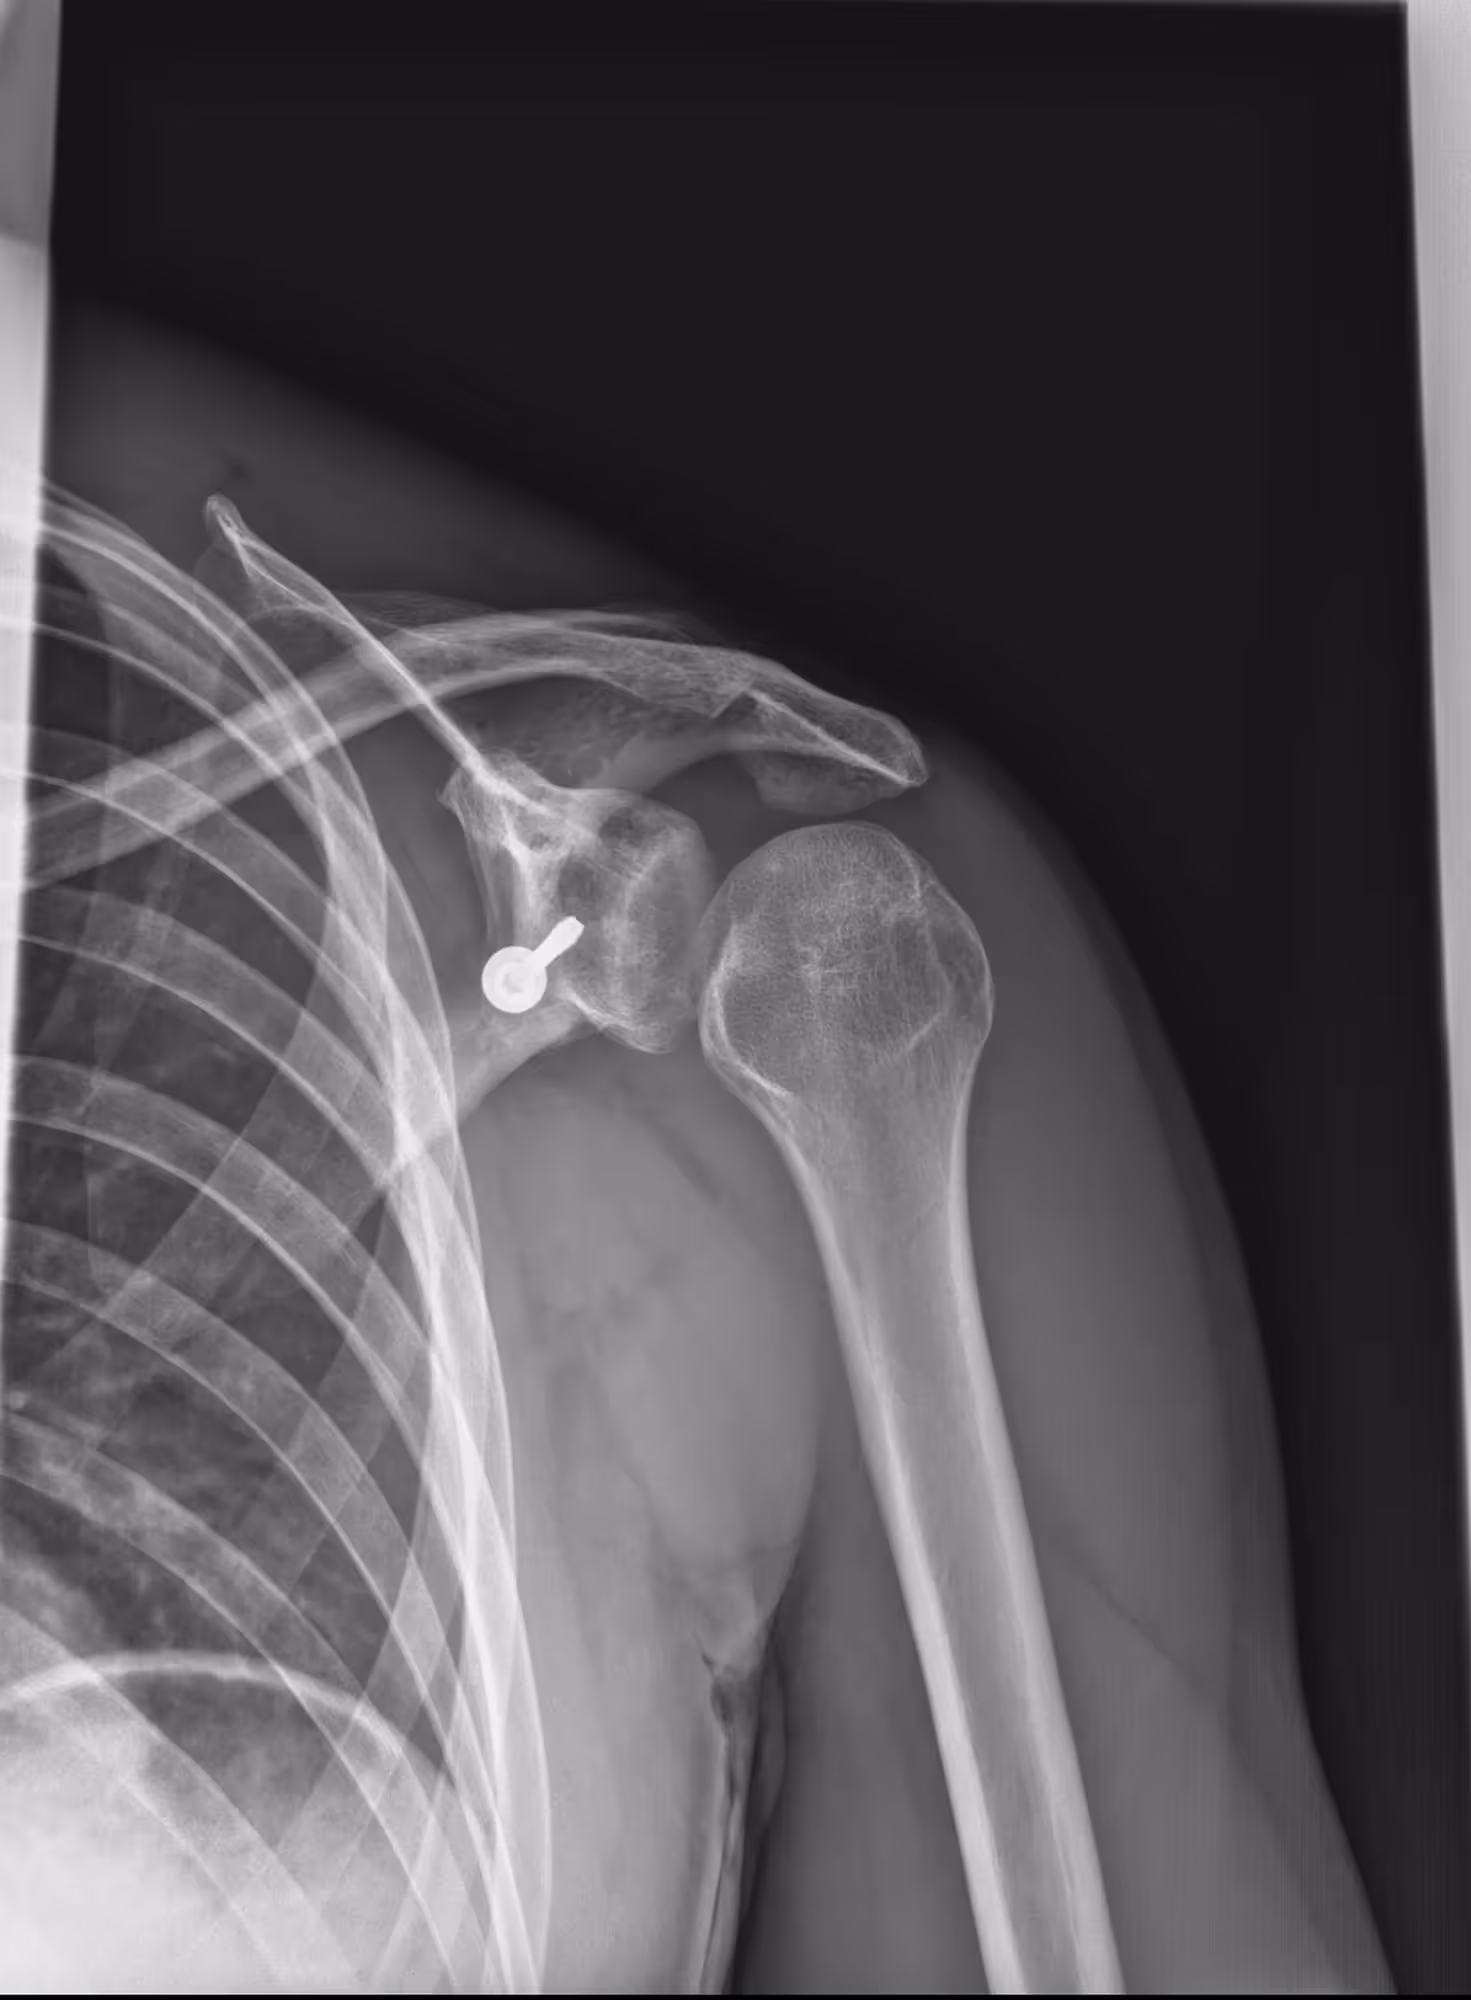

Indication

A 29-year-old male under the influence of alcohol with total functional impotence of the left arm.

Results

BoneView detected a posterior glenohumeral dislocation.